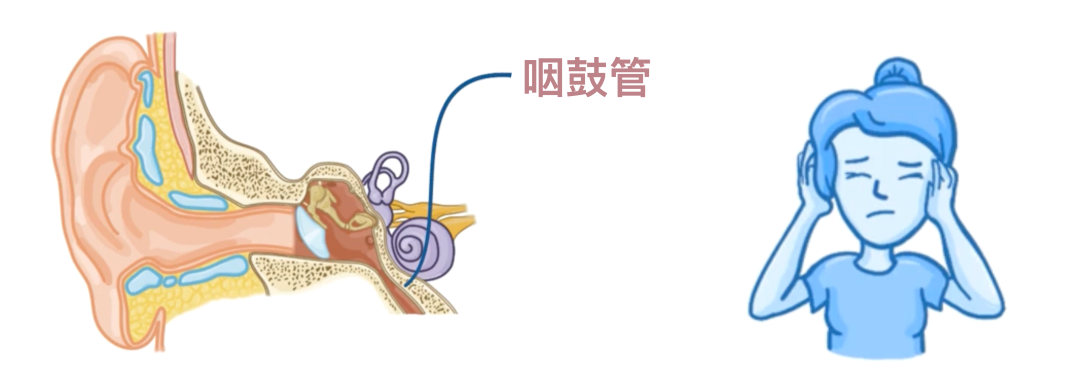

肺炎链球菌还可以侵入咽鼓管,引起中耳感染,即中耳炎,表现为疼痛和耳痛。

慢性中耳炎可能会扩散到耳后乳突小房,引起乳突炎。

最终,感染还可能从乳突小房蔓延至颅腔,这是肺炎链球菌导致脑膜炎的另一途径。